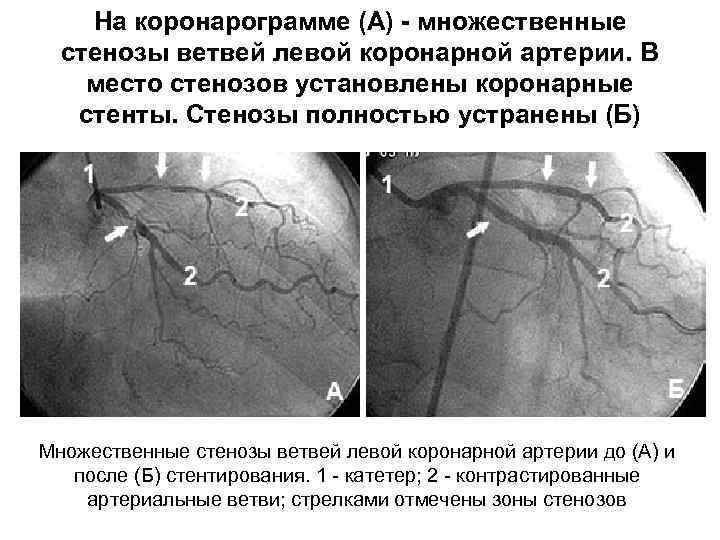

Хроническая окклюзия артерий: причины, симптомы и лечение